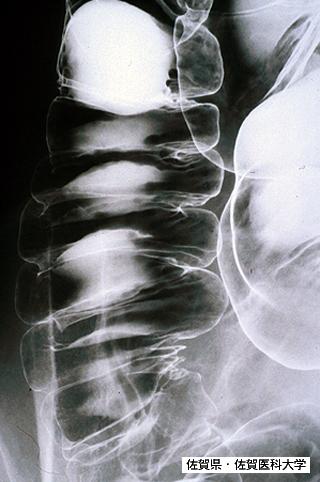

Posted by: Saga Pref., Saga Medical School (Dr.水口)

Criteria of Hist.ClassificationMalignant Lymphoma/ATL(Adult T-cell Leukemia / Lymphoma)

LocationLarge intestine(Colon)/Ascending colon

Technique, MethodX-ray